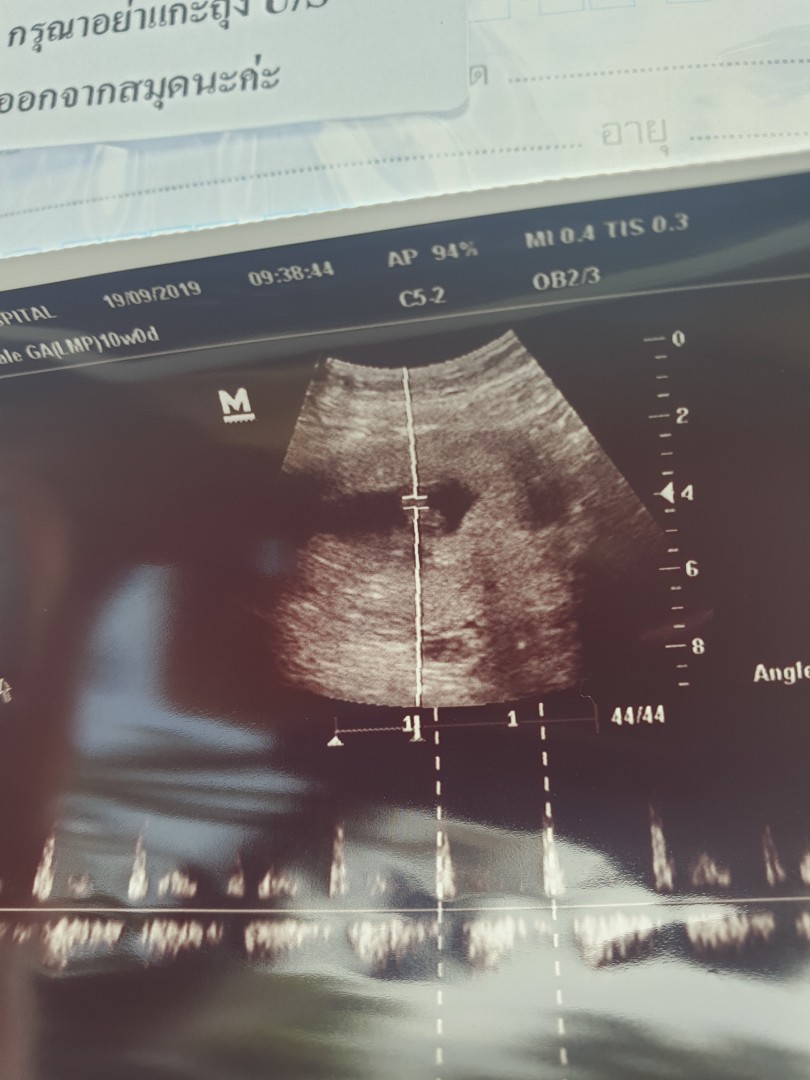

ซาวด์เจอถุงครรภ์7W4Dค่ะแต่ยังไม่เจอตัวเด็กอยากทราบว่าคุณแม่ท่านไหนเจอตัวเด็กกันกี่Wบ้างค่ะ